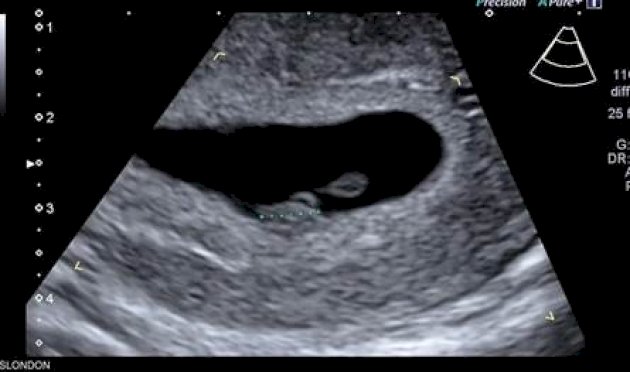

ذكاء اصطناعي يحدّد موعد الولادة بدقة غير مسبوقة عبر صور الموجات فوق الصوتية

كشفت دراسة حديثة أن الذكاء الاصطناعي قد يصبح أداة ثورية في تحديد الموعد الدقيق لولادة الأطفال، بنسبة دقة تصل إلى 95 في المئة.

لكن مجموعة من الباحثين الأميركيين تقول إن استخدام الذكاء الاصطناعي لتحليل صور الموجات فوق الصوتية يمكن أن يتنبأ بموعد ميلاد الطفل بدقة تصل إلى 95 في المئة.

وباستخدام برنامج تم تطويره وتدريبه باستخدام أكثر من مليوني صورة بالموجات فوق الصوتية لنساء أنجبن أطفالهن بين عامي 2017 و2020، قام العلماء بقياس مدى قدرة الذكاء الاصطناعي على تقدير ما إذا كان الطفل سيرى النور في موعد ولادته أم لا.

أبرز نتائج البرنامج، المسمى Ultrasound AI:

التنبؤ بموعد ولادة الطفل في حالة الحمل المكتمل بدقة بلغت 95 في المئة.

التنبؤ بالولادة المبكرة بدقة بلغت 72 في المئة، من دون الحاجة إلى بيانات إضافية مثل التاريخ الطبي للأم أو القياسات السريرية.

التنبؤ بجميع حالات الولادة (بما في ذلك المبكرة) بدقة وصلت إلى 92 في المئة.

تعليقا على هذه النتائج، قال الدكتور جون أوبراين، مدير طب الأمومة والأجنة بجامعة كنتاكي: “الذكاء الاصطناعي بات يصل إلى داخل الرحم، ليساعدنا على التنبؤ بموعد الولادة بدقة، وهو ما سيقود إلى تحسين الرعاية الصحية للأمهات في جميع أنحاء العالم”. (سكاي نيوزو)